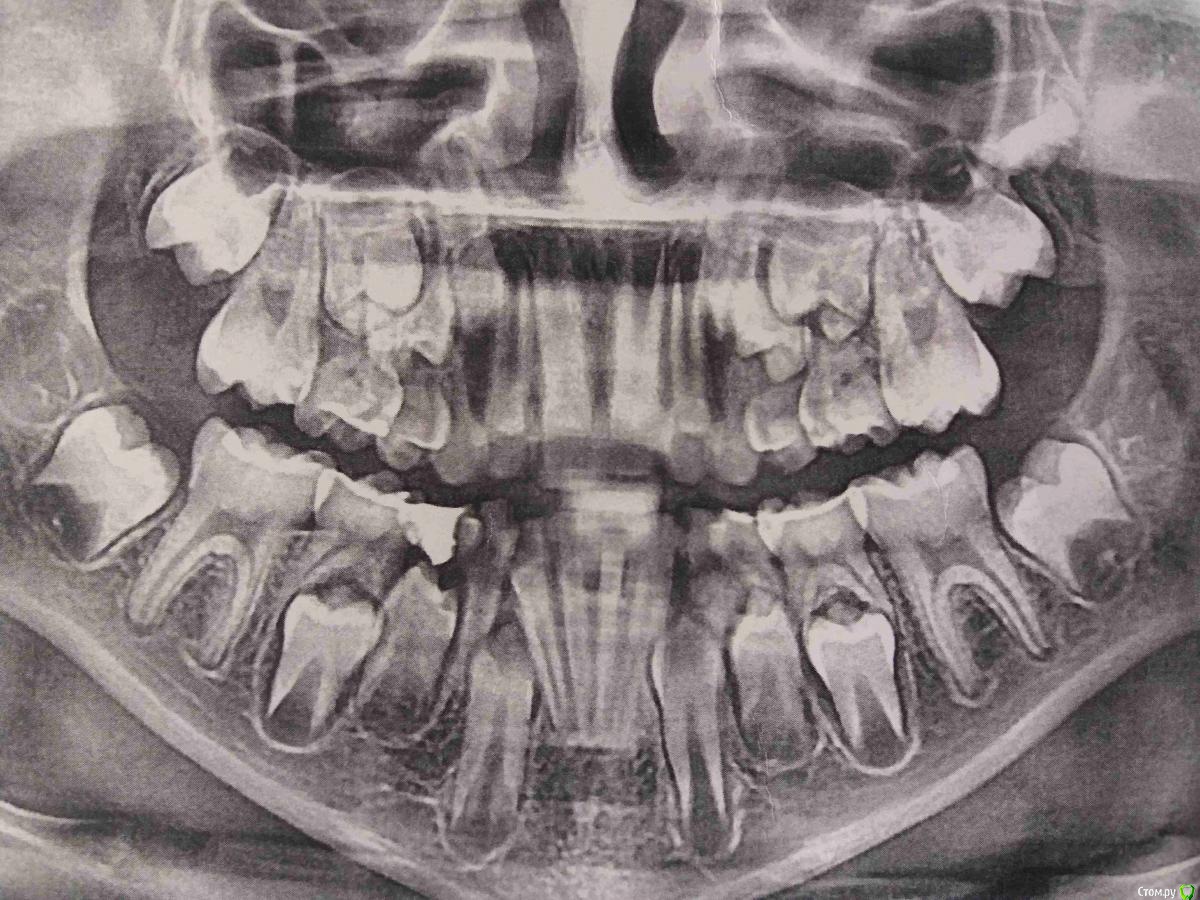

kuznetsovaev Опубликовано 13 июля, 2019 Поделиться Опубликовано 13 июля, 2019 (изменено) Здравствуйте, посмотрите пожалуйста наш снимок. Мальчик 9лет, носим пластину на нижней челюсти 10 месяцев. Но мне кажется сдвигов почти нет. Подкручиваем 1 раз в неделю на 1 деление. Может мало подкручиваем? Или пластинка возвращает сама обратно такое может быть?Видно ли на снимке скоро выпадут 4 и хватает ли места новым зубам? Может у нас есть еще какие-то проблемы прокоментируйте пожалуйста! Спасибо.Если нужно фото зубов сейчас добавлю. Изменено 13 июля, 2019 пользователем kuznetsovaev Ссылка на комментарий

Brigita Опубликовано 16 июля, 2019 Поделиться Опубликовано 16 июля, 2019 Расширение нижней челюсти без расширения верхней не эффективно 2 Ссылка на комментарий

kuznetsovaev Опубликовано 17 июля, 2019 Автор Поделиться Опубликовано 17 июля, 2019 Сходили к другому врачу. Его вариант лечения: удаление нижних троек и четверок с обеих сторон. И потом новая пластина на низ и на верх. Как считаете стоит довериться этому врачу? Ссылка на комментарий

Дмитрий Л. Опубликовано 18 июля, 2019 Поделиться Опубликовано 18 июля, 2019 Удалять тройки не стоит. Менять доктора тоже. Сфотографируйте пластинку. Сдвигов не может не быть. Ссылка на комментарий